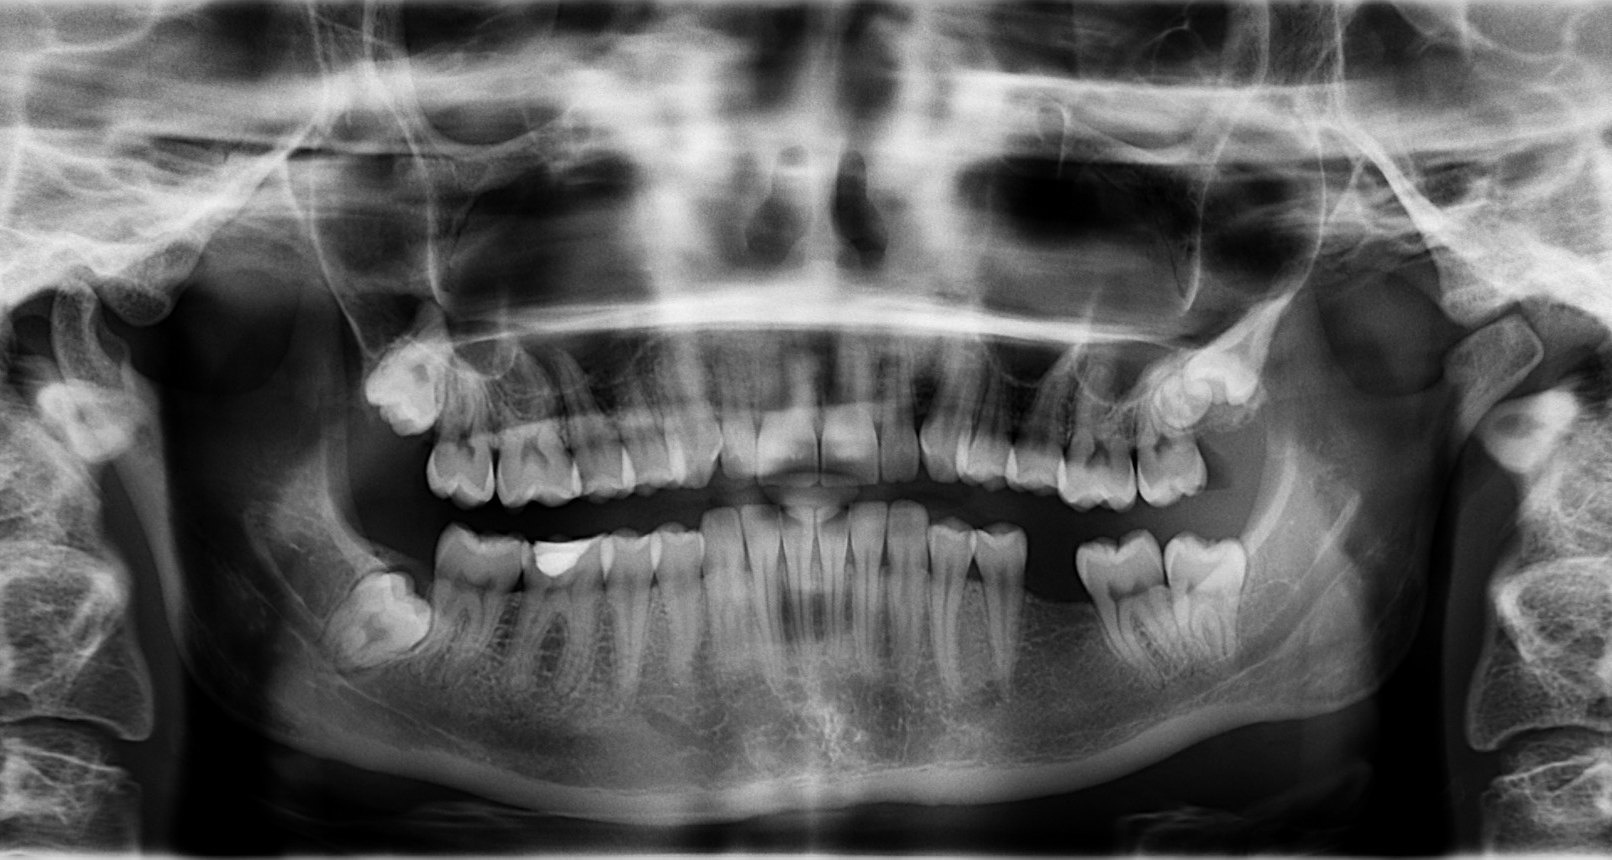

Почему зубы не считаются костью

Наши зубы, как и кости, твердые и белые. И на этом, пожалуй, сходство двух частей человеческого тела заканчивается. А дальше начинаются различия, коих наберется два товарных вагона: начиная от химического состава, заканчивая механическими и биологическими функциями. Объясняем научно-популярным языком, почему зубы точно не кости, а кости точно не зубы.